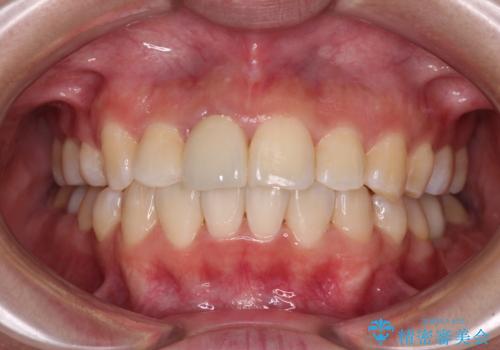

前歯のがたつき 深い噛み合わせを改善したい